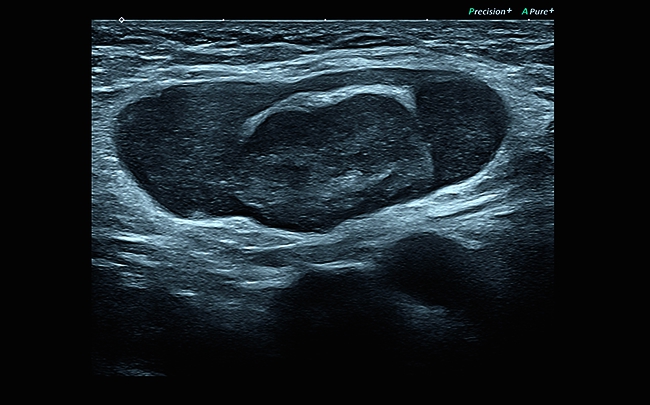

• Технология Precision Imaging

• Технология ApliPure+: многолучевое сканирование в реальном времени для повышения качества изображения

• Технология MicroPure для обнаружения небольших концентраций солей кальция